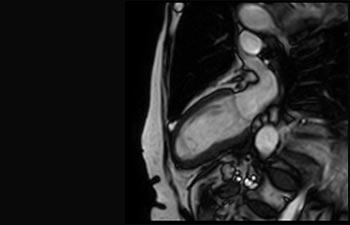

Akuter Myokardinfarkt